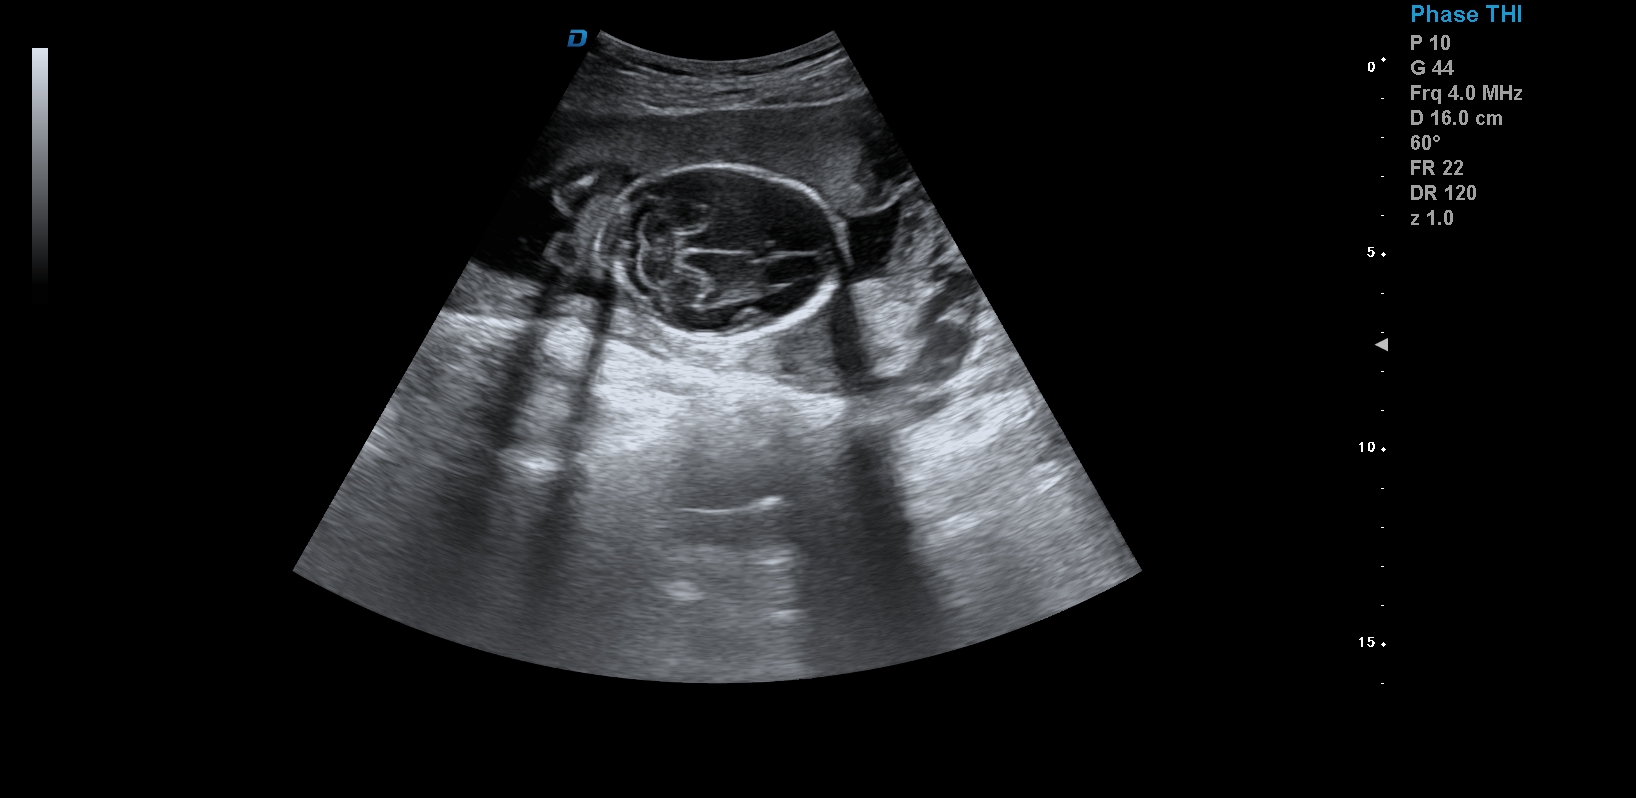

首先,四維彩超檢查是采用高清晰度的彩超儀對胎兒進行各個心臟器官及組織的一次全面檢查,可以立體顯示胎兒的發育情況,胎兒在子宮內的任何狀態都可以觀察到。對胎兒畸形能夠早診斷,及時地做出相應的措施,以達到優生優育的標準。

四維彩超不但成像清晰,更是在三維的基礎之上附加時間這個矢量。這就在排畸的同時能時刻觀察寶寶在宮內的一舉一動,吃手指、打哈欠、吮吸……寶寶在宮內憨態可掬,讓孕媽媽母愛井噴,幸福不已。這也是孕媽媽們選擇四維的主要原因,試想,誰不想在辛苦懷孕期間提前看一看自己寶寶的模樣呢?

1、四維彩超是目前先進的彩色超聲技術.能直觀立體現實人體器官動靜態三維結構,一定程度上提高臨床診斷的準確性。

3、清晰成像:采用先進的超聲成像技術,擁有高清晰,高分辨率、高精確度優點,能清晰看到包括生殖器、內臟器官在內的胎兒的各個部位發育情況.

四維彩超最佳時間是24-26周。這個時候胎兒結構發育完善,可觀察到大多數的胎兒畸形。胎兒30周左右最好再去做一次四維彩超,因為胎兒結構是一個逐漸發育的過程,畸形沒有發展到一定程度可能不能被檢查到。